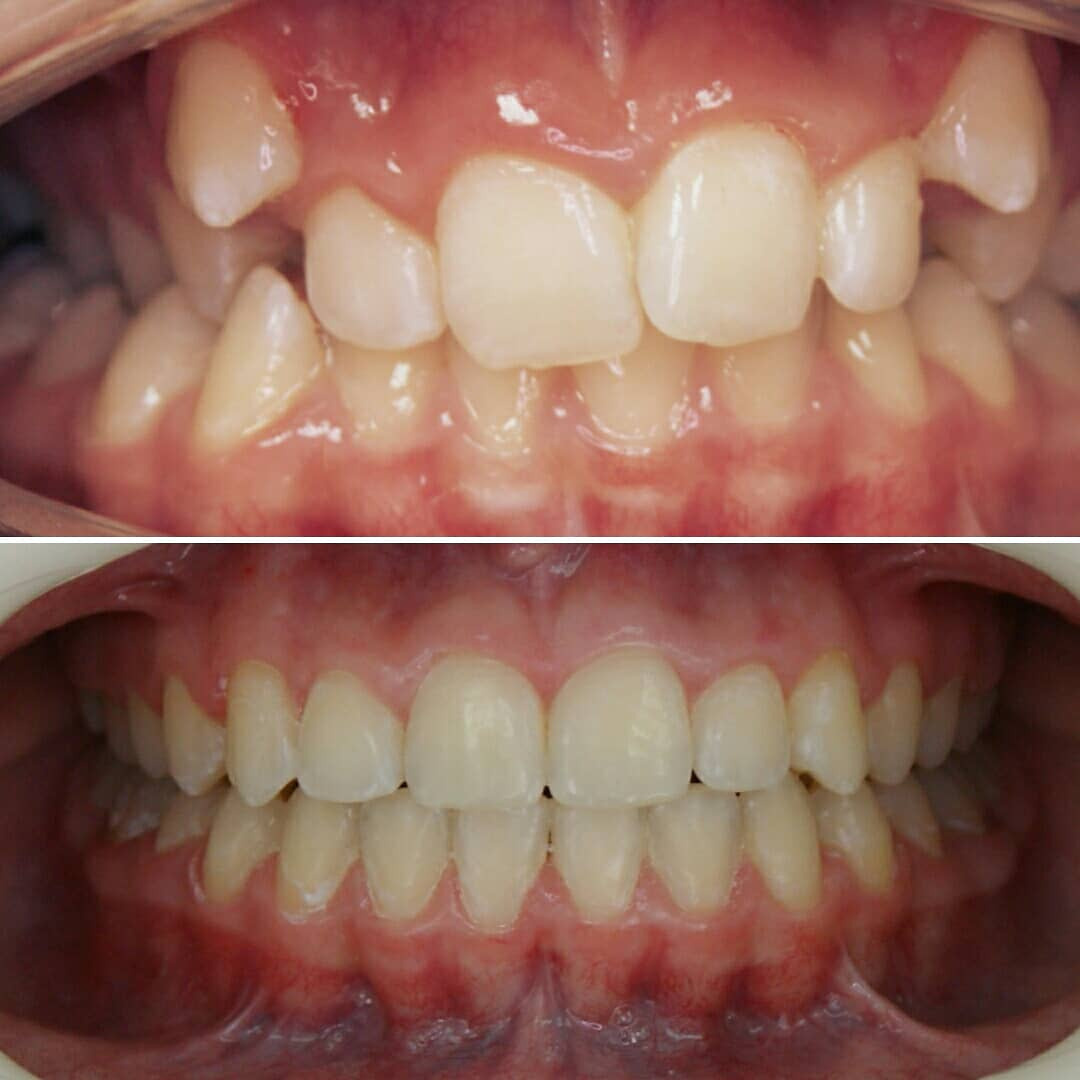

✔Глубокий прикус, дистальный прикус с пространством (щелью) между верхними и нижними резцами, скученное положение зубов, заблокированное нёбное положение верхнего левого зуба ✔Лечение на металлической самолигирующей системе Damon

✔Пациент, 12,5 лет на момент старта ✔Общий срок лечения 18 месяцев ✔Брекеты Damon Q ✔Дистальный, перекрестный, глубокий прикус, смещение нижней челюсти, несоответствие средних линий и сужение зубных рядов, скученность зубов, недостаток места для верхних клыков